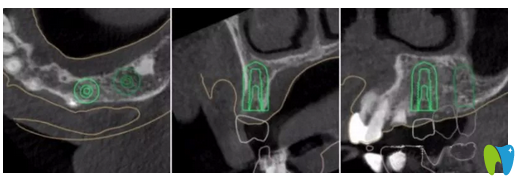

▲ 患者左上4牙位模擬種植圖

應(yīng)患者要求,并考慮到患者自身因素(高齡、高血糖及高血壓史),本著拜博口腔精 準(zhǔn)種牙的原則,擬定出數(shù)字化導(dǎo)板種植合并傳統(tǒng)修復(fù)的治療方案:

① 一期16,17,24,26數(shù)字化全程導(dǎo)板引導(dǎo)種植,二期16,17單冠修復(fù),24,25,26連橋修復(fù)。